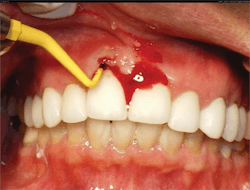

Technical issues include occlusal trauma, implant breakage, loosening of screws and abutments, and fracture, which can occur in screws, abutments, and/or porcelain. It should be emphasized that these are just a few of many potential problems (figure 1).

Both disease and corrective treatment can result in compromised esthetics. Frequently, implant esthetics are compromised due to exposed threads and abutments. This invites plaque and debris to harbor in the area.

There are many choices in restorative options, and many result in highly esthetic final results. However, these restorations can make cleaning a difficult, if not impossible, challenge for the patient (figure 2).